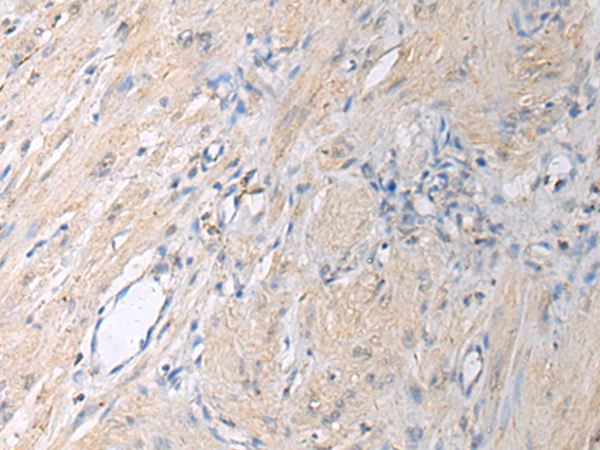

分类: 科研抗体货号: P10401别名: Gi应用: WB,IHC反应种属: Human, Mouse, Rat